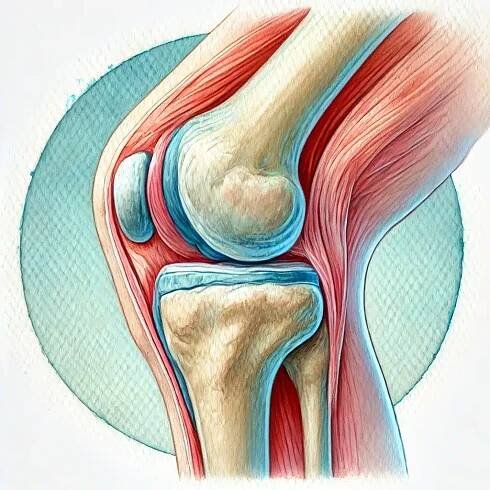

Gonartróza, osteoartróza kolenního kloubu neboli artróza kolenního kloubu je degenerativní onemocnění kolenního kloubu. Gonartróza způsobuje bolest a ztuhlost v oblasti kolene, a může komplikovat každodenní činnosti, jako je vstávání ze židle nebo i krátké procházky.

Co je kolenní gonartróza?